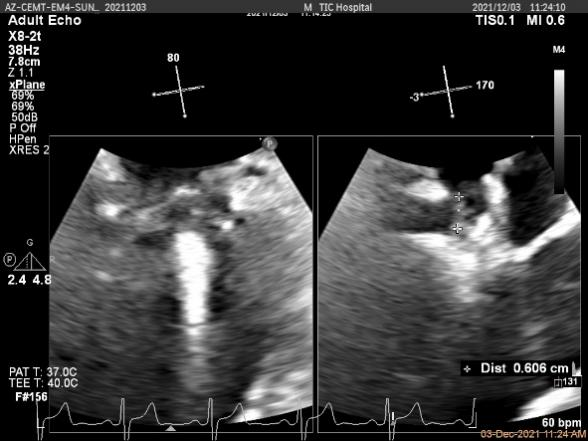

X-plane:下夹子尝试先捕获1区脱垂瓣叶

x-plane平面测量确认后叶抓捕长度大于6mm

3D证实夹子AC区残余脱垂被禁锢住